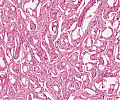

A92 Follikuläres Adenom der Schilddrüse

Randlicher Anteil mit mikrfollikulärem Aufbau (hohe Vergrößerung)

-

A92 Follikuläres Adenom der Schilddrüse

Randlicher Anteil mit mikrfollikulärem Aufbau (geringe Vergrößerung)

Follikuläres_Adenom1_SD_A92.png

Neoplastische Follikel unterschiedlicher Größe von isomorphen Follikelepithelien mit sog. Resorptionsvakuolen begrenzt

Follikuläres_Adenom_SD_A92.png

Follikulär gebaute Neoplasie mit gemischt mikro und normo-follikulärem Aufbau, umgeben von einer bindegewebigen Pseudokapsel.